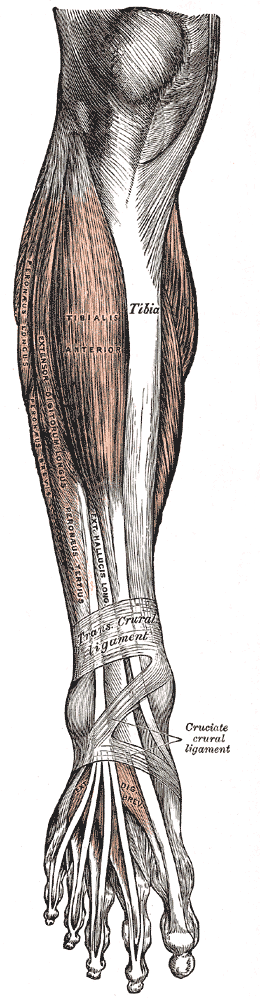

Muscles of the front of the leg. (Ext. halluc. long. labeled vertically at center.) | |